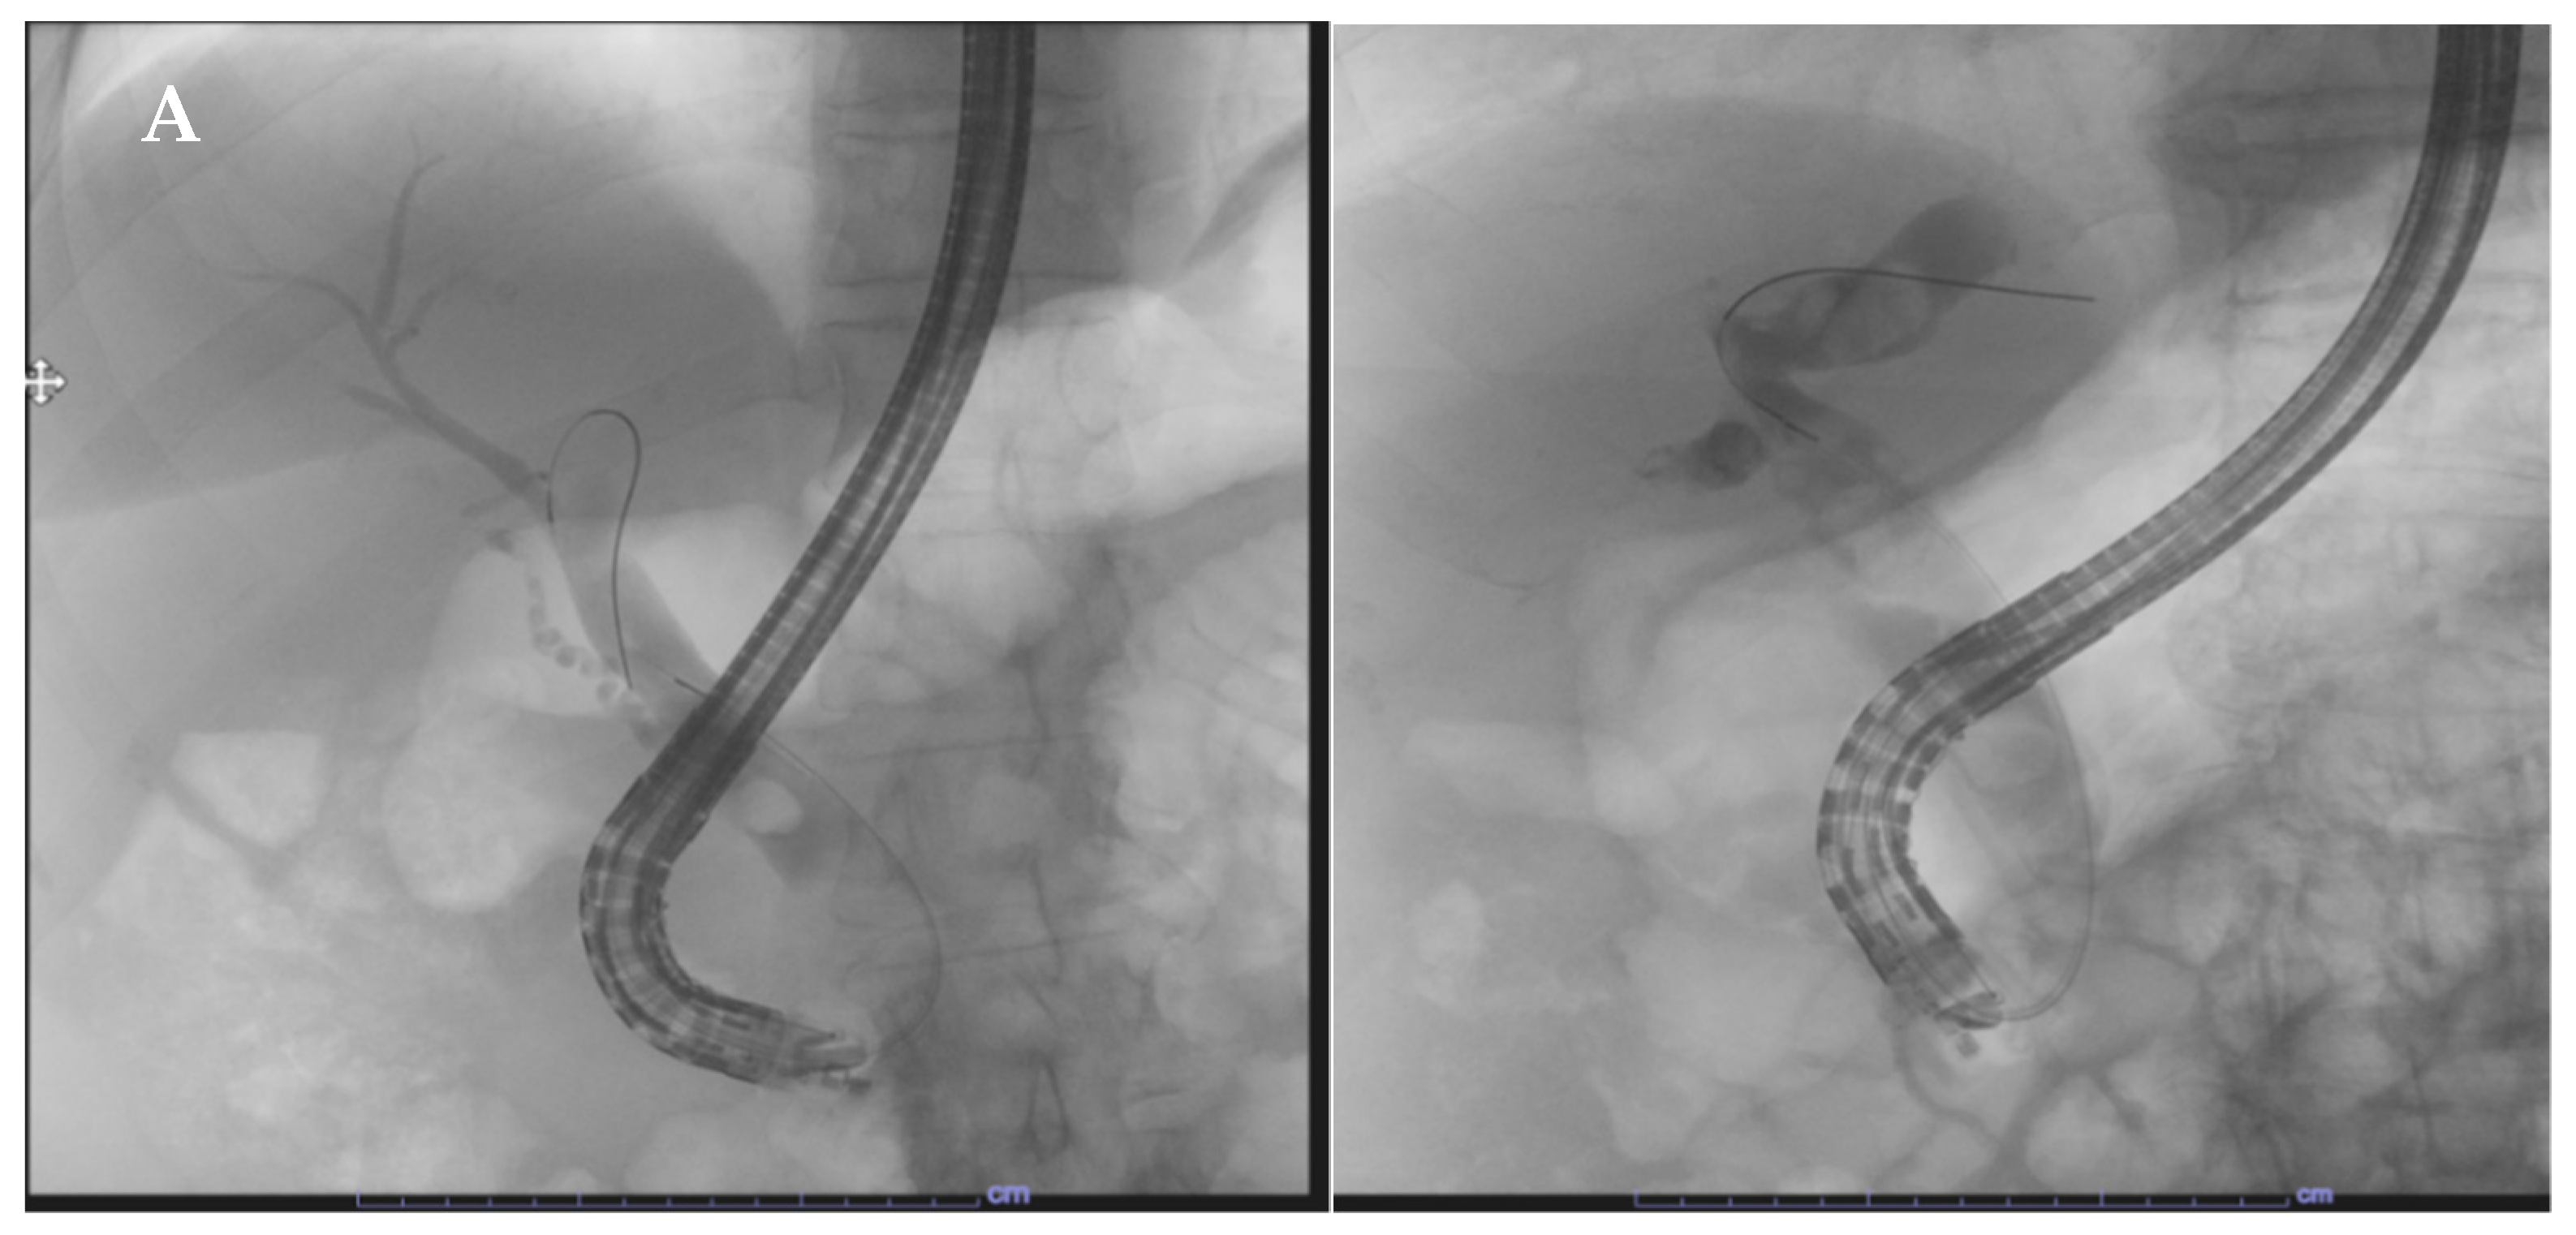

- Rivallin, P.; Lorenzo, D.; Hedjoudje, A.; Prat, F. Single-use duodenoscopes are an efficient tool for emergency ERCP in real life. Endosc. Int. Open 2022, 10, E1497–E1500. [Google Scholar] [CrossRef] [PubMed]